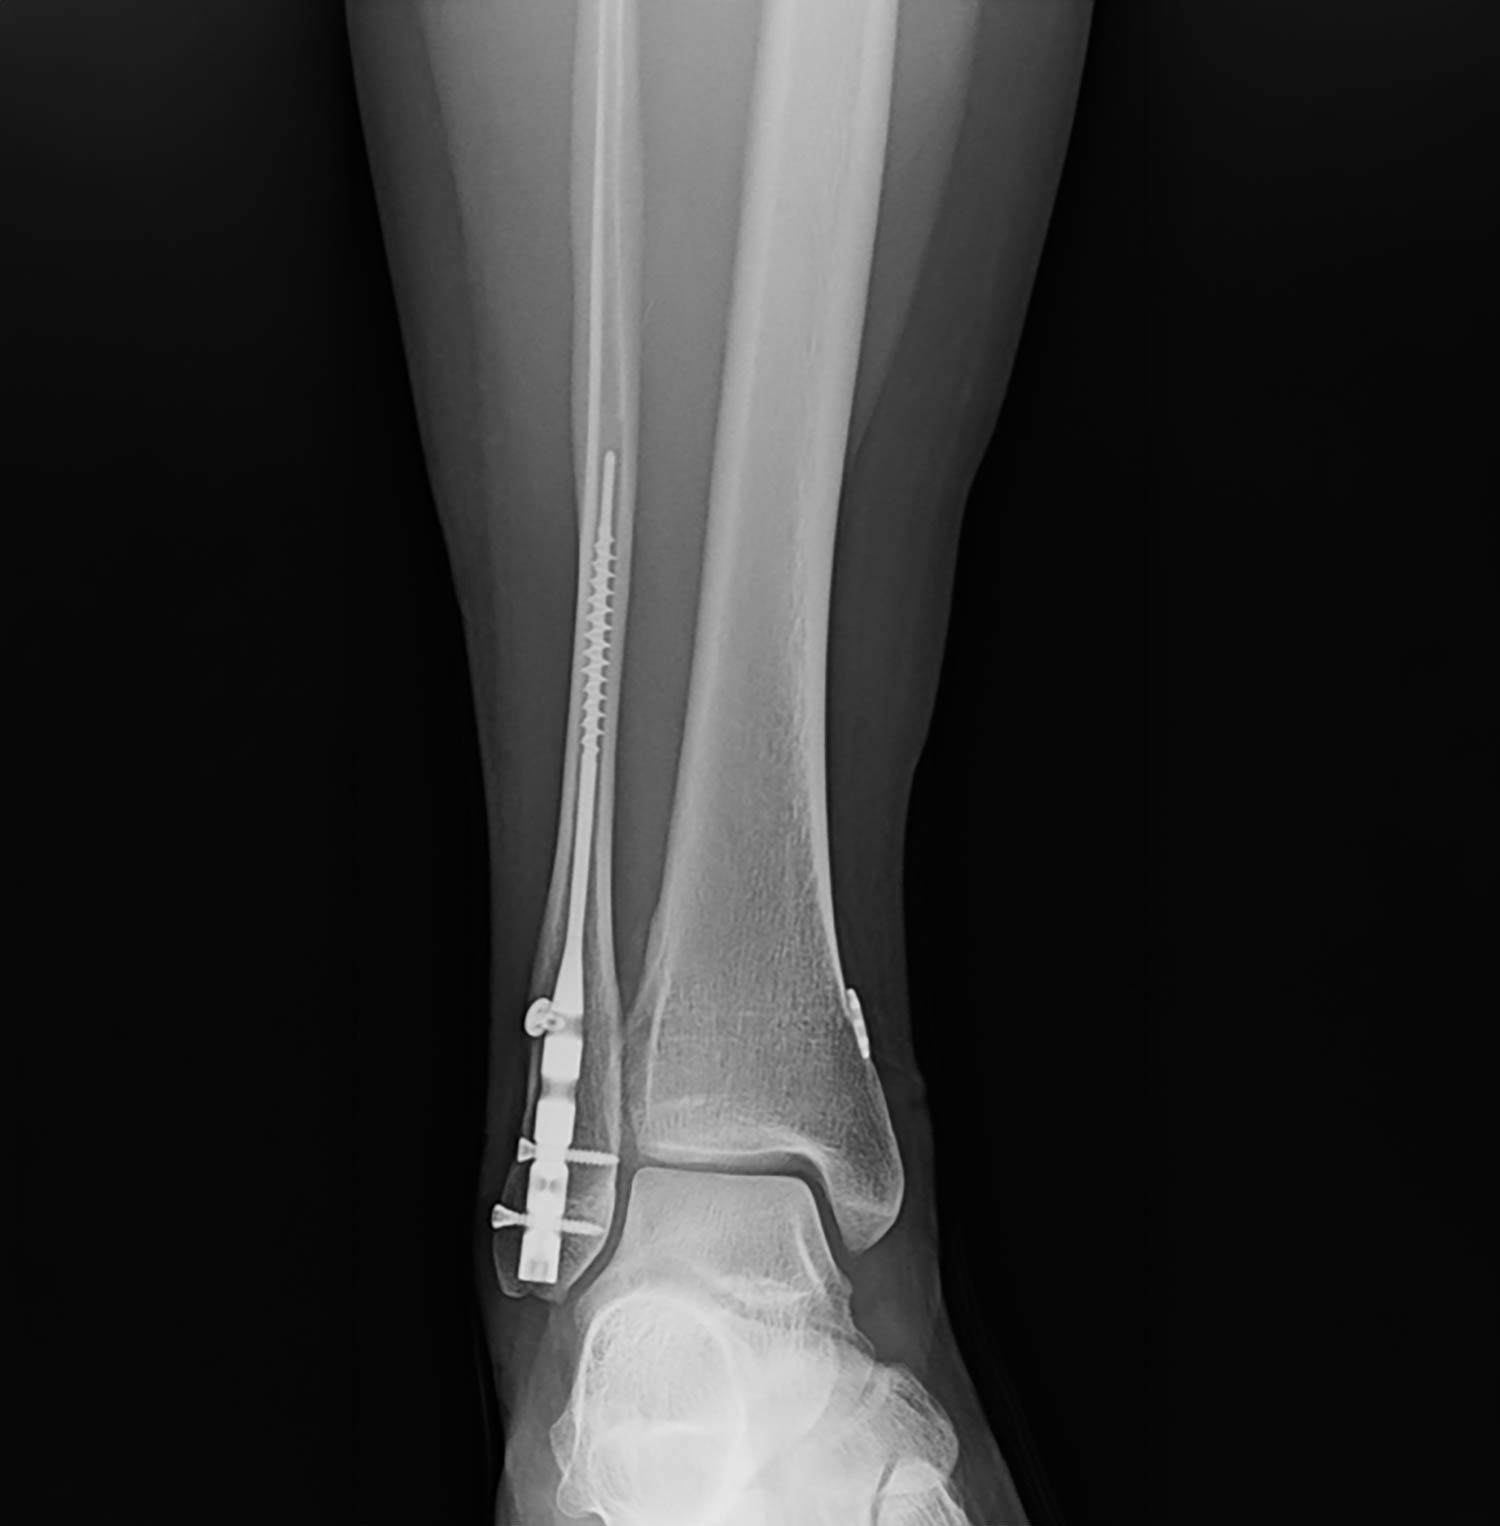

The transition from traditional Open Reduction Internal Fixation (ORIF) with plates and screws toward intramedullary fibular nailing represents a significant paradigm shift in ankle fracture management. While historically reserved for “train wreck” patients–those with compromised soft tissue, diabetes, or advanced age–current clinical evidence suggests that fibular nails are highly effective for simpler fracture patterns, such as stress-positive Weber B fractures.

- Modern Primary Indications: Simple, stress-positive Weber B fibular fractures. These patients benefit from minimally invasive surgery (MIS), zero hardware prominence, and small incisions.

Weightbearing and Recovery Outcomes

One of the most significant advantages of fibular nailing is the ability to accelerate weightbearing protocols.

Average Time to Weightbearing (Study Data)

- Isolated Fibular Fractures: 3.9 weeks

- Bimalleolar Fractures: 3.3 weeks

- Trimalleolar Fractures: 5.1 weeks

- Pilon Fractures: 6.8 weeks

Current Clinical Practice: For isolated fibular fractures fixed with a nail, some surgeons now permit immediate postoperative weightbearing in a CAM boot. This is rarely possible with traditional plating due to the size of the incision and the increased risk of wound dehiscence with early mobilization.

Radiographic vs. Functional Outcomes

The study utilized the McLennan and Ungersma guidelines to qualify reductions as “good,” “fair,” or “poor.”

- Reduction Accuracy: 97% of cases were reduced to length; 100% achieved closure of the medial clear space.

- Acceptable Displacement: Approximately 9% of cases showed “fair” reduction, often involving a 1–2 mm posterior displacement. This is frequently due to the syndesmotic screw/button passing through the fracture site.

- Clinical Relevance: There is no documented clinical difference in functional outcomes between “good” and “fair” radiographic reductions. Because the fibula is largely extra-articular, a “functional reduction” (restoring gross anatomy, length, and rotation) is sufficient for patient satisfaction and long-term success.